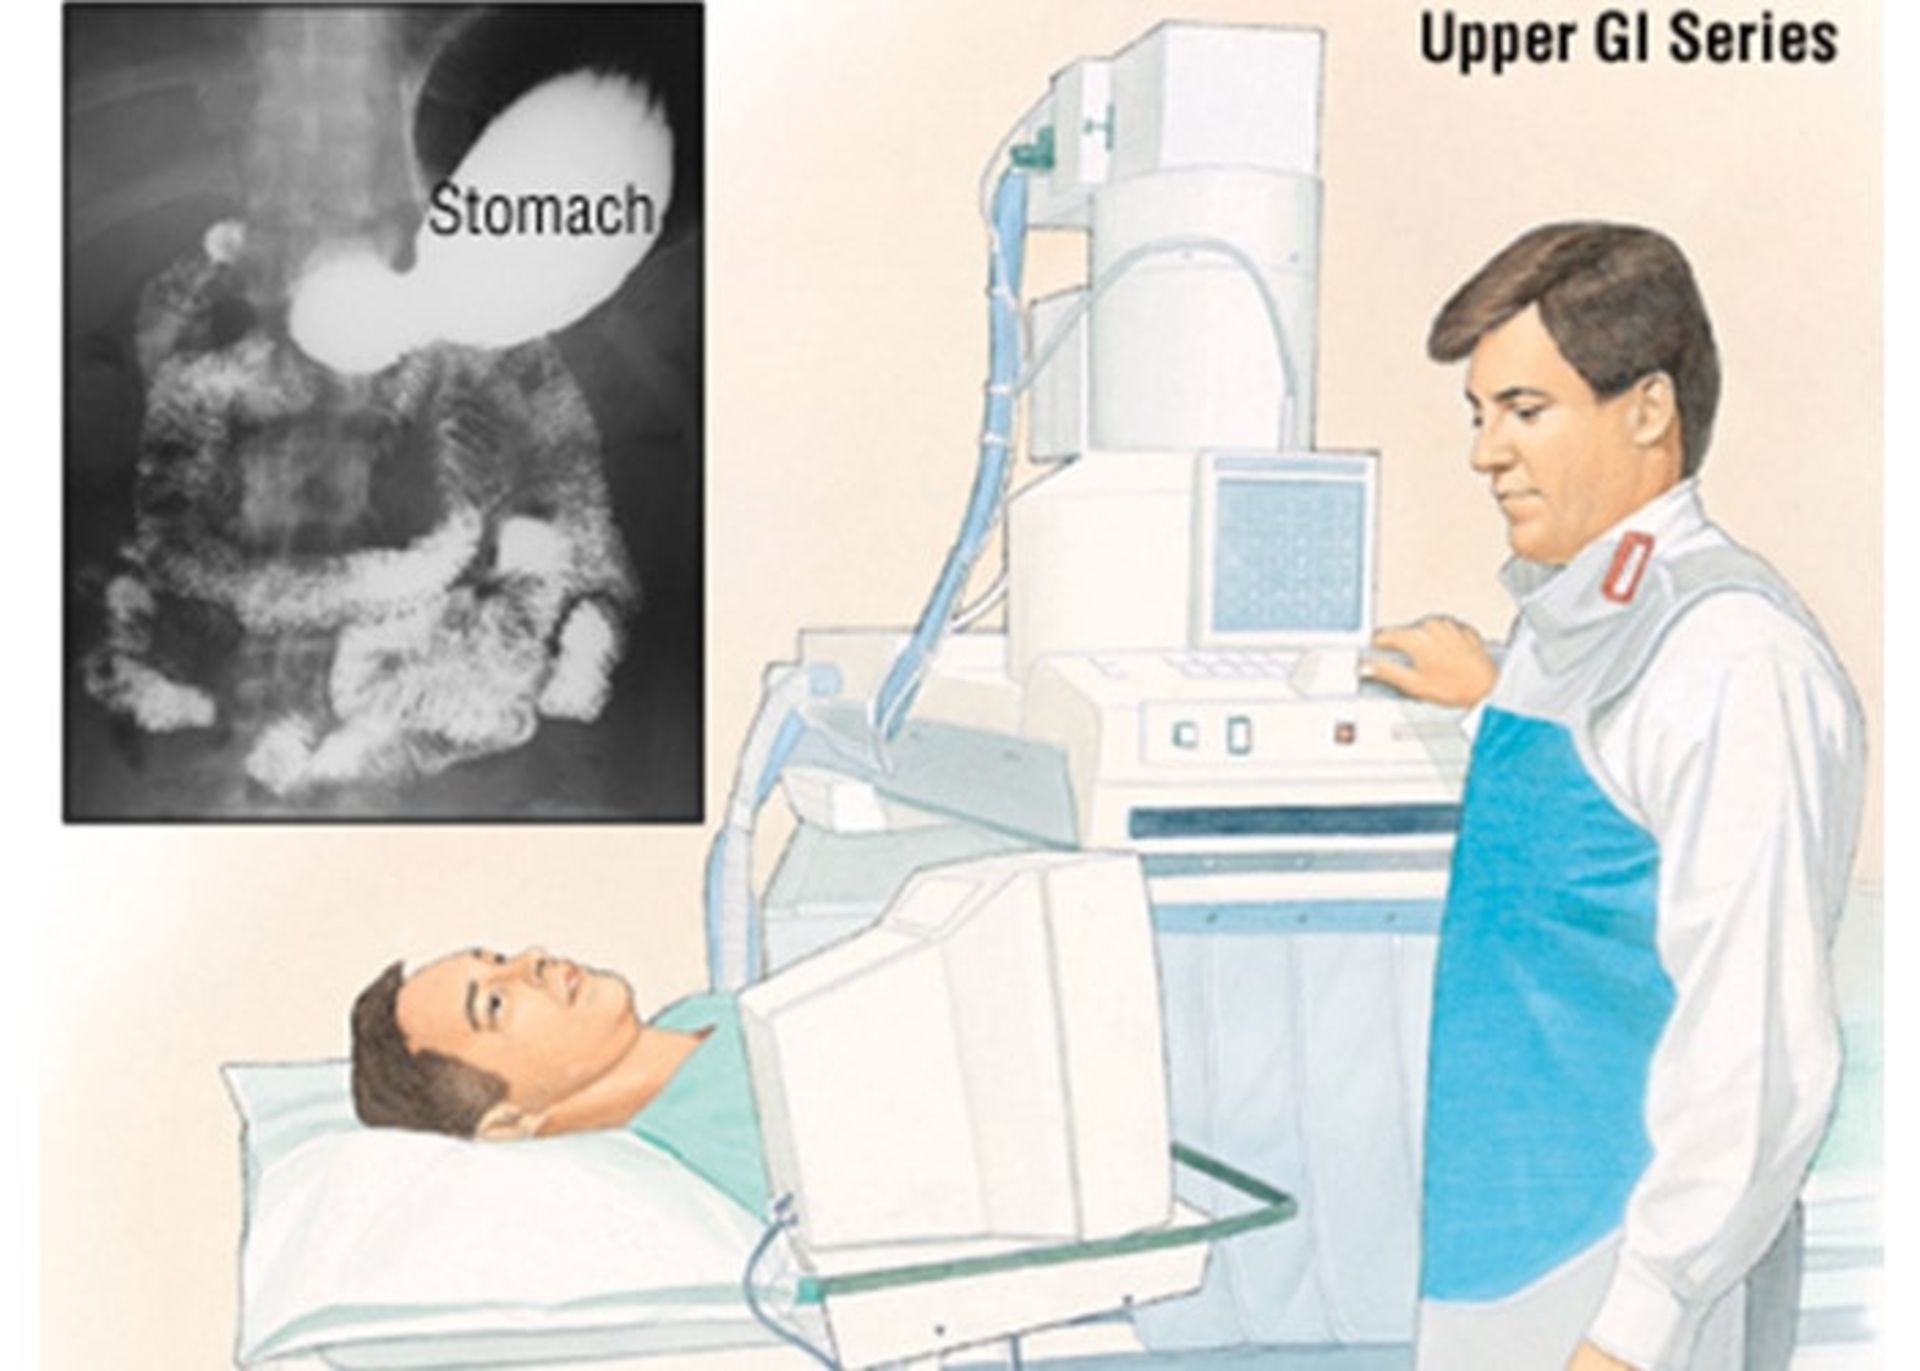

آزمایشهای تصویربرداری سری GI: در این آزمایش با استفاده از اشعهی ایکس پوشش داخلی مری، معده و بخش ابتدایی رودهی کوچک مورد بررسی قرار میگیرد. این روش نسبتبه آندوسکوپی، کمتر برای تشخیص سرطان معده یا دیگر مشکلات معده استفاده میشود زیرا ممکن است برخی از مناطق غیرطبیعی را نشان ندهد و نیز به پزشکان امکان نمونهبرداری از بافت را نمیدهد. البته این روش نسبتبه آندوسکوپی کمتر تهاجمی است و در برخی موقعیتها میتواند مفید باشد.

بهمنظور انجام این آزمایش، بیمار یک محلول گچمانند سفید را که حاوی باریوم است، مینوشد. باریوم روی پوشش مری، معده و رودهی کوچک مینشیند. سپس چندین تصویر اشعهی ایکس گرفته میشود. از آنجایی که اشعهی ایکس قادر به عبور از باریوم عبور نیست، این عکسها میتوانند وجود هر ناهنجاری در پوشش این اندامها را نشان دهند. برای تشخیص سرطان معده در مراحل اولیه، از تکنیک کنتراست دوگانه نیز استفاده میشود. در این روش بعد از اینکه بیمار محلول باریوم را خورد، یک لولهی نازک وارد معده او میشود و ازطریق آن هوا بهداخل معده پمپ میشود. این امر نازک شدن لایهی باریوم را به دنبال دارد و حتی ناهنجاریهای کوچک نیز نمایان خواهند شد.